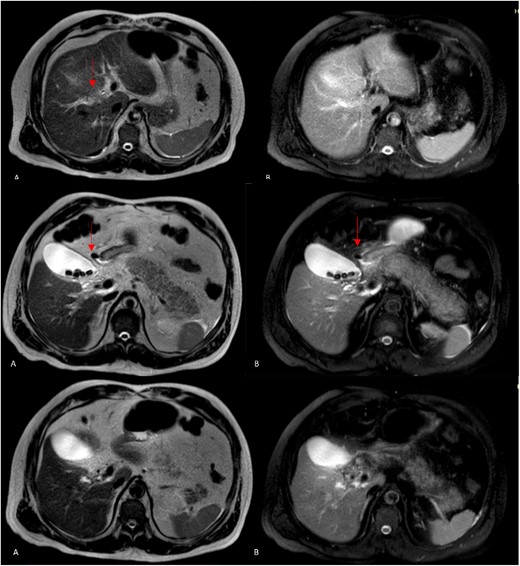

A 61-year-old Mexican man presented to the emergency room with an epigastric pain; he was admitted due to acute pancreatitis of biliary origin and intermediate risk of choledocholithiasis. We performed a magnetic resonance reported, right posterior hepatic duct absence of signal, choledochal with presence of heterogeneous content with absence of signal in intrapancreatic portion of a choledochal duct (Fig. 1). On the endoscopic retrograde cholangiopancreatography (ERCP), a cystic drain of the RHD was found (Fig. 2). Patient presented slow clinical evolution with increased systemic inflammatory response syndrome for which a contrasted computer tomography was performed with findings of pancreatitis with Balthazar C score. Subsequently, an adequate evolution was presented, and the acute picture of pancreatitis is resolved, hospital discharge was performed to an elective laparoscopic cholecystectomy of interval.

Magnetic resonance cholangiopancreatography (MRCP) axial imagen. A: T2W- TSE; B, T2W- SPIR. A and B findings right posterior hepatic duct absence of signal, choledochal with presence of heterogeneous content with absence of signal in intrapancreatic portion (arrows).